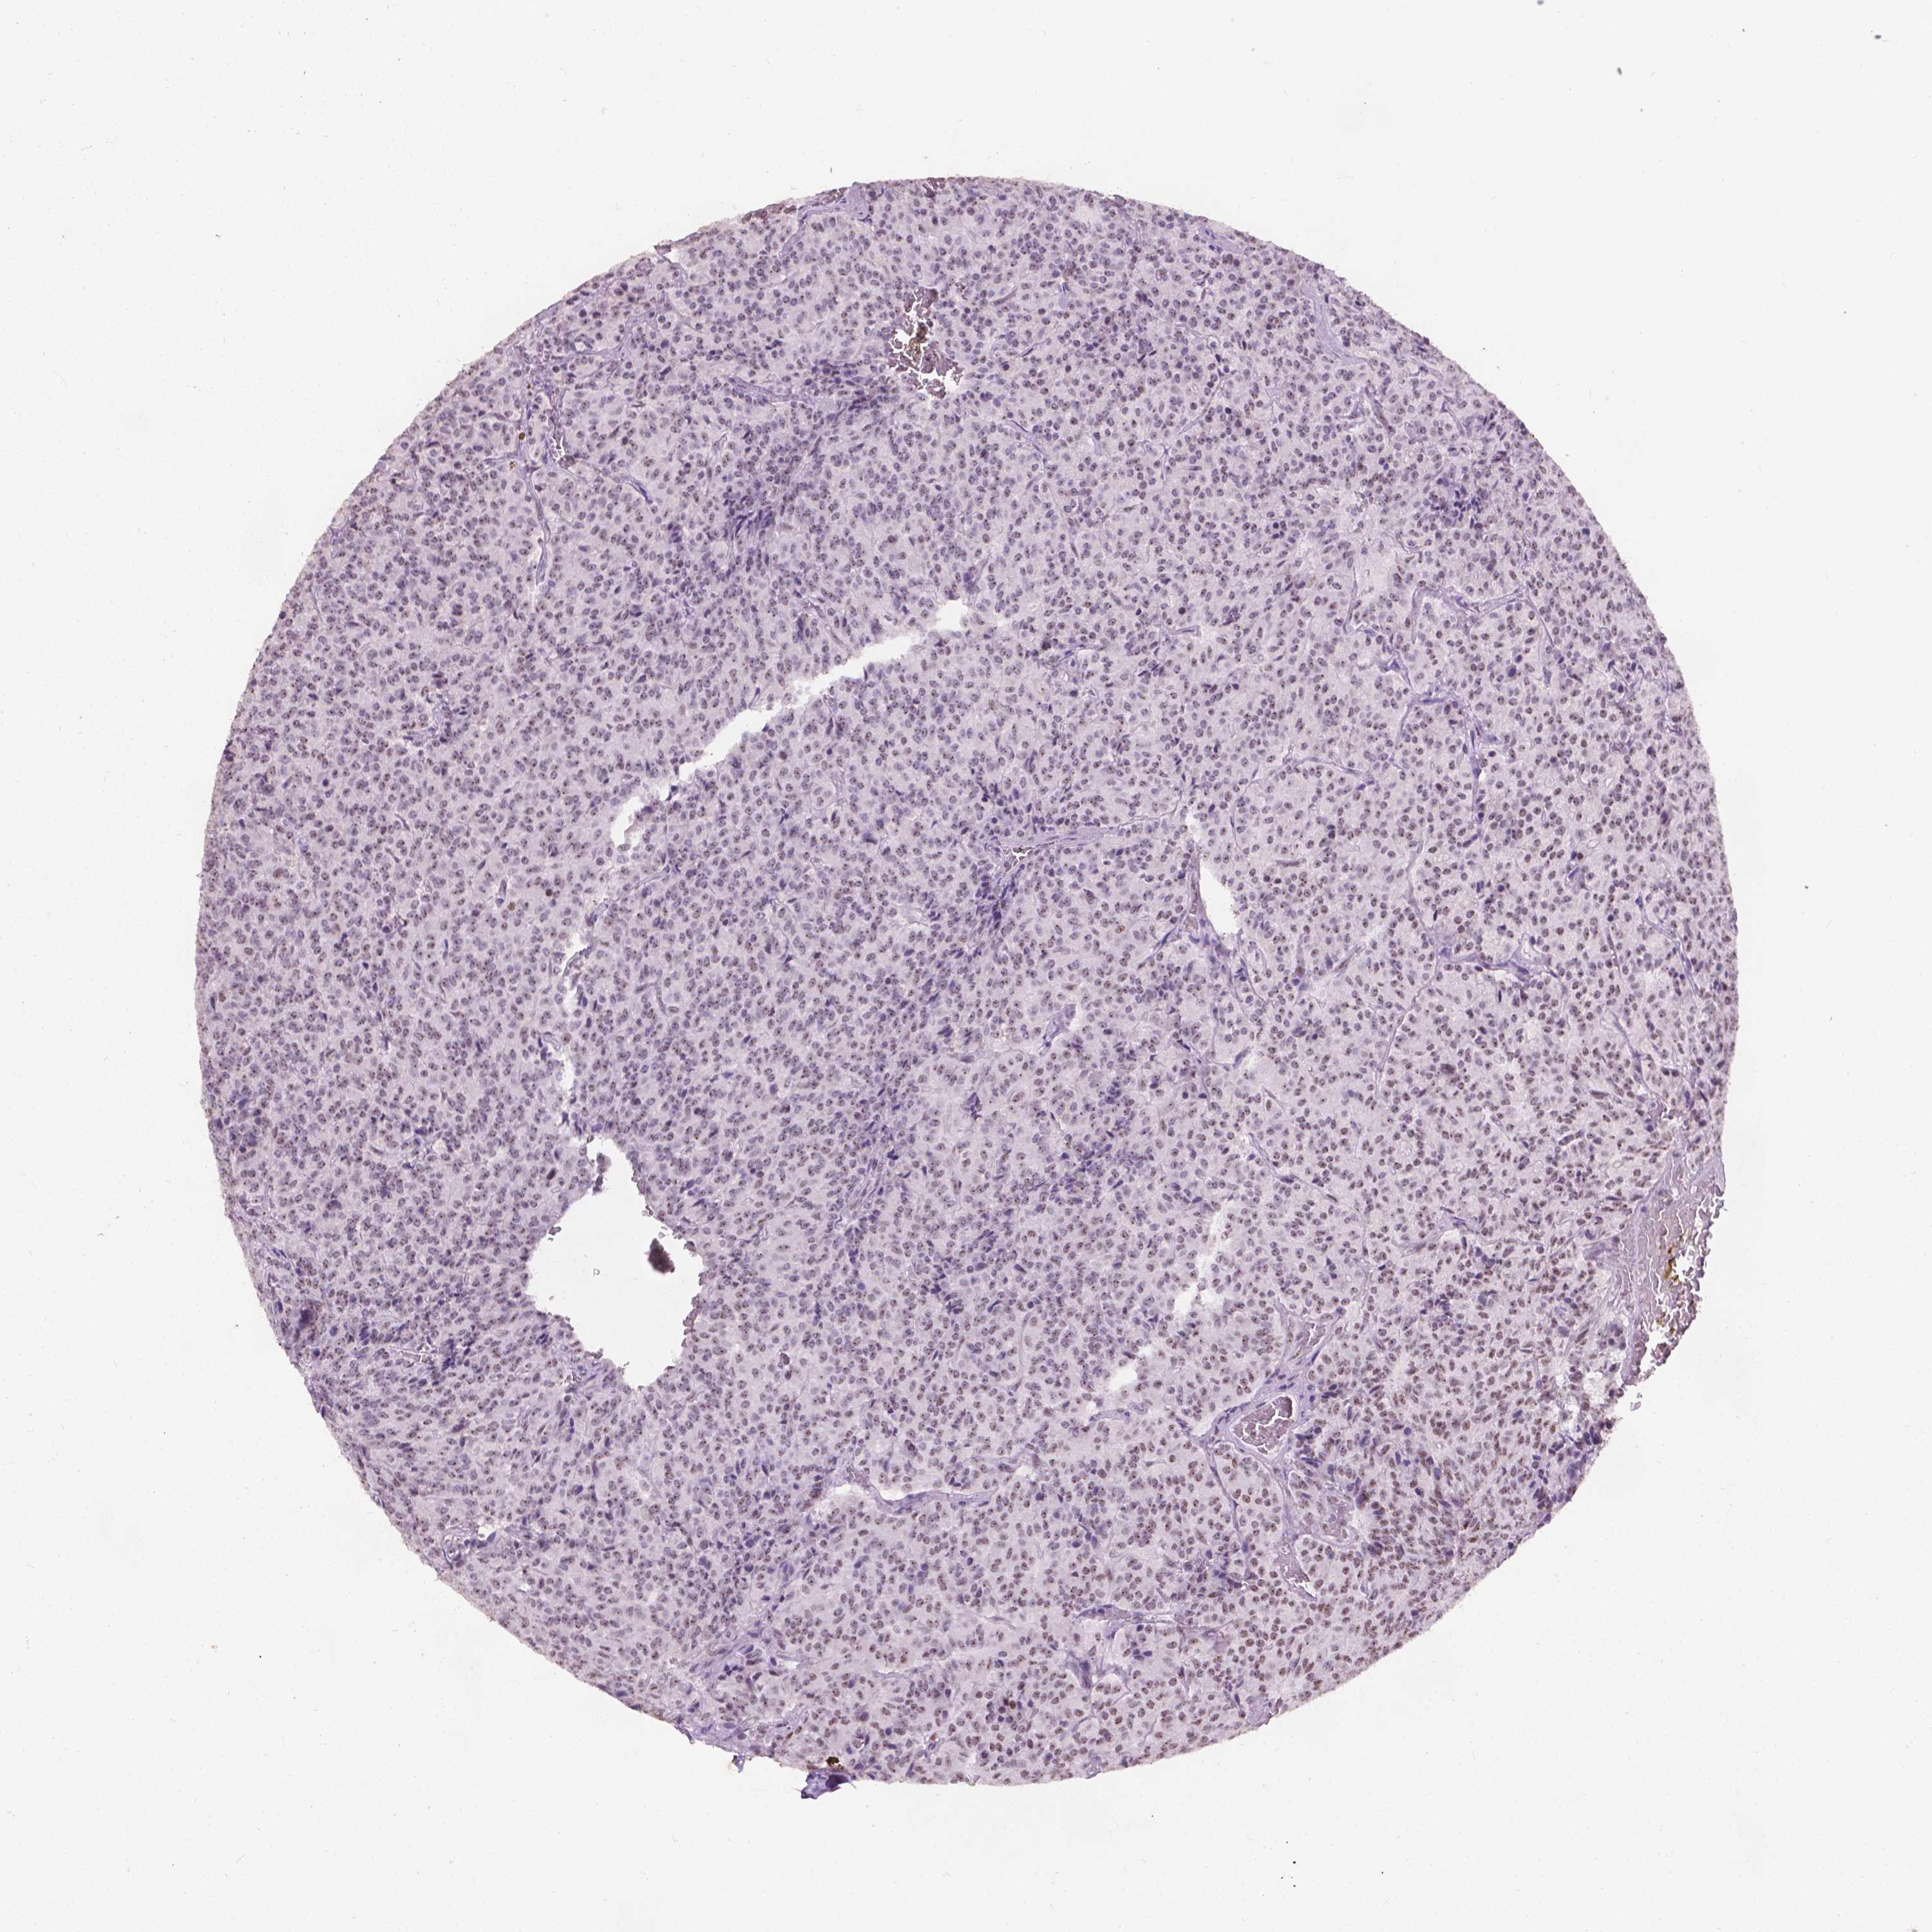

CARCINOID - Protein expressioni

A mouse-over function shows sample information and annotation data. Click on an image to view it in a full screen mode. Samples can be filtered based on level of antibody staining by selecting one or several of the following categories: high, medium, low and not detected. The assay and annotation is described here.

Each image is clickable and will lead to virtual microscopy that enables deeper exploration of all samples and also displays staining intensity scores, fraction scores and subcellular localization as well as patient and tissue information for each sample.

Antibody CAB069400

Staining

High

Intensity

Strong

Quantity

>75%

Location

Nuclear

Carcinoid, malignant, NOS